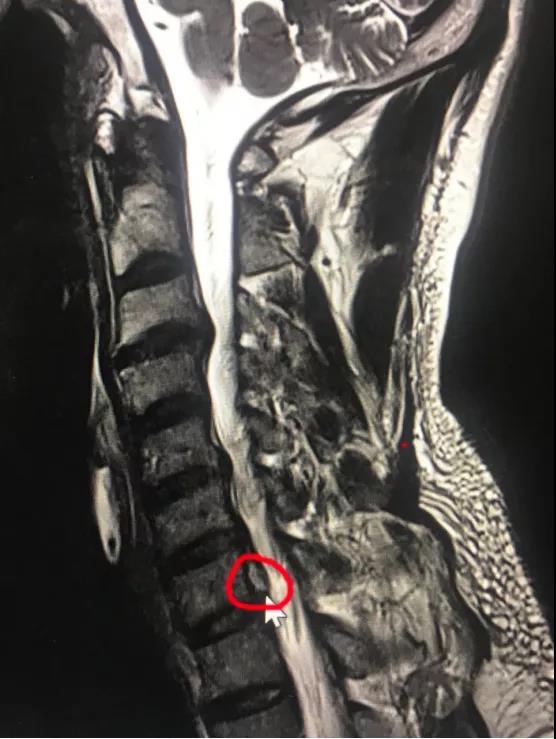

颈椎前路间盘摘除椎管减压植骨融合内固定(ACDF)是经典的手术方式,但要牺牲一个颈椎运动节段。近日,*安泰**市中心医院脊柱外科收治宁阳患者张某,45岁,颈部不适2月,右上肢疼痛麻木1月余。采用牵引、药物等治疗,效果欠佳。疼痛无法缓解,严重影响睡眠。入院诊断颈椎间盘突出症,完善X线、CT、MR相关检查显示:颈6/7椎间盘突出,向下方脱垂至颈7椎体中下方,压迫脊髓。由于颈椎椎间盘突出高度脱垂,至椎间隙下方较远,采用传统ACDF,从前方椎间隙根本无法取出脱垂的间盘组织。科室采用局部麻醉,颈椎后路“钥匙孔”技术,通过在颈7右侧椎板用高速磨钻磨出一个7毫米的小孔,直达病变部位,将高度脱垂的间盘顺利取出,患者术后疼痛即刻消失,由于局部麻醉,增加了手术的安全性,患者术后就能够正常下床活动,手术第2天出院,受到了患者及家属的好评。

神经根型颈椎病是最常见的颈椎病类型,由于颈椎神经根活动度较小,“黄豆”大小的的颈椎间盘突出就可以引起剧烈疼痛,脊柱外科开展脊柱内镜治疗颈椎间盘突出技术(“钥匙孔”技术)已经有3年时间,具有“三好一满意”(1、外观好,颈部后方只有7毫米切口,一般愈合以后看不到切口;2、内镜下视野好,放大约4-10倍,清晰,完全不破坏脊柱稳定性,不需内固定,微创,安全;3、疗效好,通过透视定位,直达患处,直接解除神经压迫;4、患者满意,术后即刻解除症状,早期下地,早期恢复工作生活。)的优势。脊柱外科通过此技术已治愈近100例患者,都收到取得良好的治疗效果。该患者高度脱垂型的颈椎间盘突出采用内镜下颈椎后方椎板“钥匙孔”技术,是在掌握熟练的颈椎内镜技术的情况开展的,此手术的成功开展,标志着*安泰**市中心医院脊柱外科颈椎内镜技术又跨上一个新的台阶。